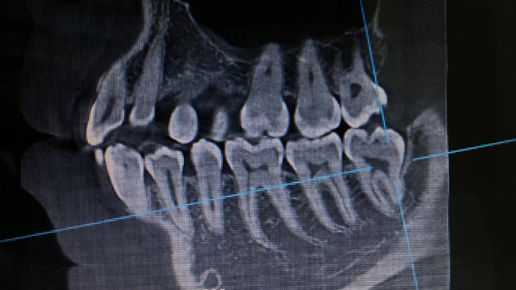

🦷Удаление зуба - это не страшно🦷

dr.Prus🦷 Сегодня поговорим о процедуре, которую многие откладывают до последнего из-за необоснованного страха — удалении зуба. Знакомая ситуация? Вы получаете направление на удаление, и сердце начинает биться чаще, а в голове возникают не самые приятные картины. Но давайте посмотрим правде в глаза: стоматология давно шагнула вперёд, и то, что раньше казалось чем-то пугающим, сегодня стало обычной, безопасной и безболезненной процедурой. В этом посте мы разберёмся, почему удаление зуба — это не повод для паники, а всего лишь один из этапов заботы о своём здоровье...